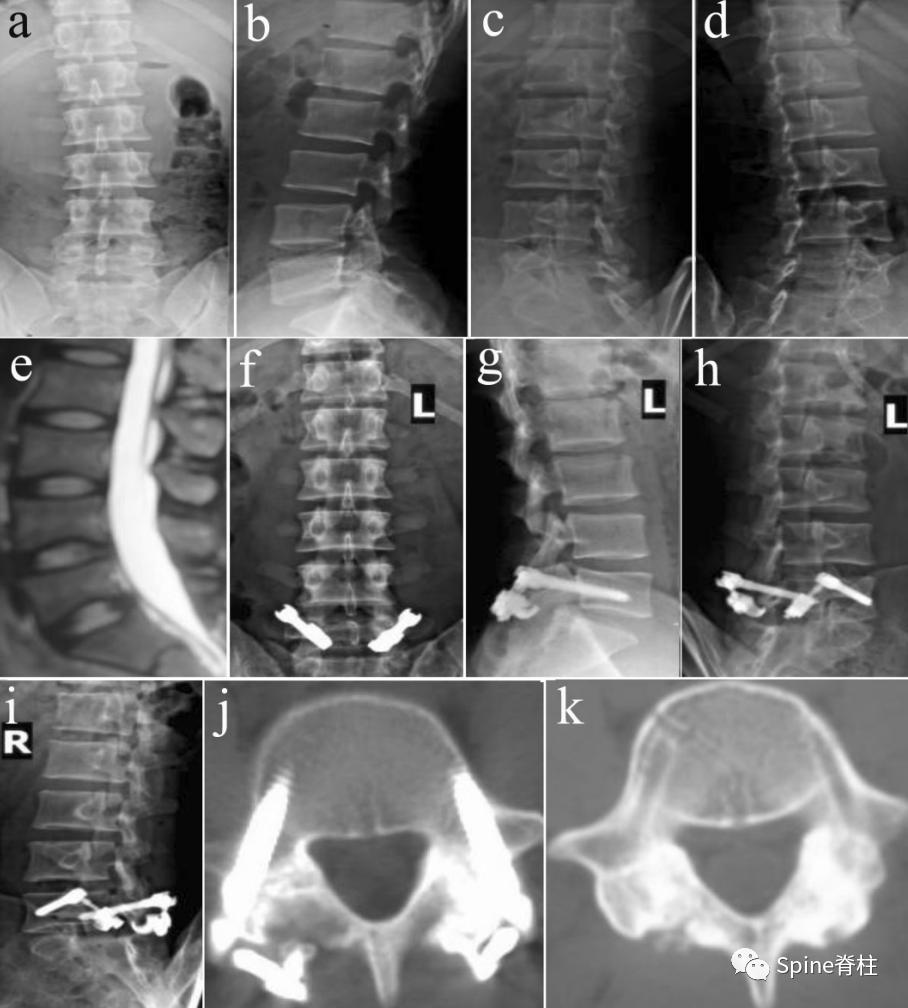

2019年国内解放军总医院第七医学中心李放教授团队。根据临床特点和影像学表现将所有病例分为3型:

- A型为单纯型峡部裂,无椎间盘突出及腰椎滑脱;

- B型为峡部裂伴有轻度椎间盘突出或I度滑脱,无神经压迫症状及体征;

- C型为峡部裂合并I度或Ⅱ度滑脱并椎间盘突出同时有神经压迫症状及体征。

并建议保守治疗无效的青年战士A、B型腰椎峡部裂病例采用椎弓根螺钉固定,峡部自体髂骨原位植骨融合率高,效果好,C型战士峡部裂则宜采用后路椎间植骨融合椎弓根螺钉内固定术。